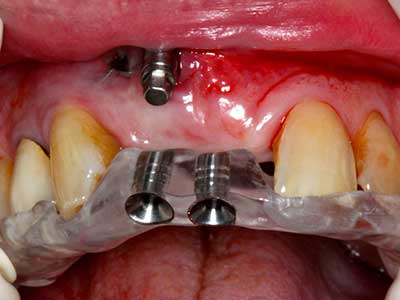

Когато се извършват хирургични процедури върху кост в непосредствена близост до чувствителни структури като кръвоносни съдове или нерви, ротиращите инструменти създават значителен риск за ятрогенно нараняване. Пиезоелектрическите апарати могат да бъдат от помощ при препарация на костно покритие и отстраняване на твърда кост близо до нерви, особено за оголване на нервите след ятрогенно нараняване, както и по време на латерализация на нервите за резекционни и реконструктивни процедури или поставяне на имплант (Фиг. 17-20). Лекият контакт между пиезонакрайника и нерва по принцип не води до нараняване, но ако действате непредпазливо с трионообразни движения или приставки за остатъчен костен субстрат, може да причините временно или перманентно увреждане на нерва. Въпреки това, рискът от увреждане се счита за много по-малък, отколкото при употреба на триони или ротиращи инструменти (Pereira, Gealh et al. 2014).

Както е показано в миналото, всяка костна хирургия представлява възможна индикация за пиезохирургия. По този начин, за препарацията на подвижни сегменти в остеогенеза (Фиг. 23-25) и остеотомия се използват специални накрайници, без да се застрашава снабдяването с кръв в кресталната зона, което е от съществено значение за успеха и на двете техники (Gonzalez-Garcia, Diniz-Freitas et al. 2008).

За отстраняването на имплант, вестибуларното костно покритие, което е заменено след премахване на импланта, може да бъде оформено, за да задържи контура на алвеоларния гребен.